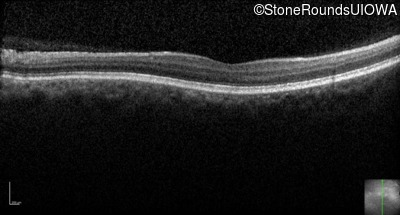

Optical Coherence Tomography - Left - 20/200

Exemplar / OCT Stack

OCT Stack